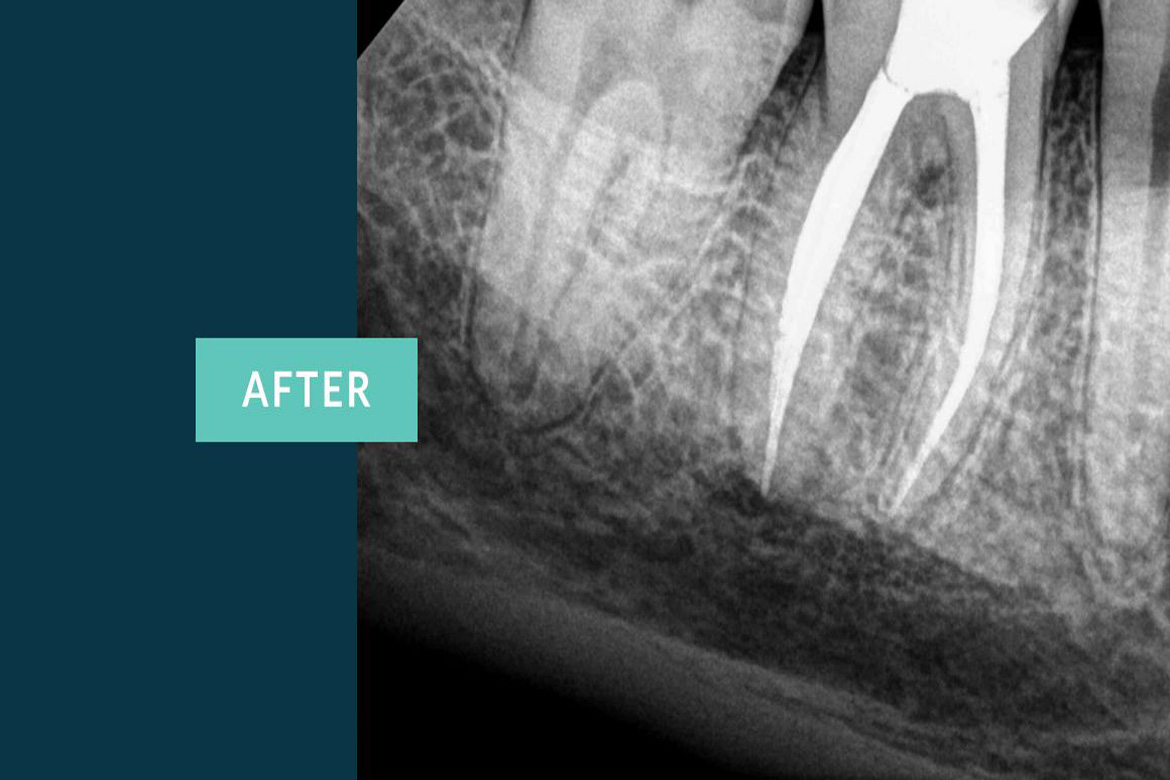

The primary intent of Root canal treatment is to remove the diseased pulp ,clean ,cleanse ,irrigate shape and then fill the canals of the tooth.

Root canal is filled completely with an inert material called Guttaperchathis is to advocate periradicular healing and prevent reinfection of the tooth there by preserving the natural tooth thus maintaining the balance in the oral cavity.